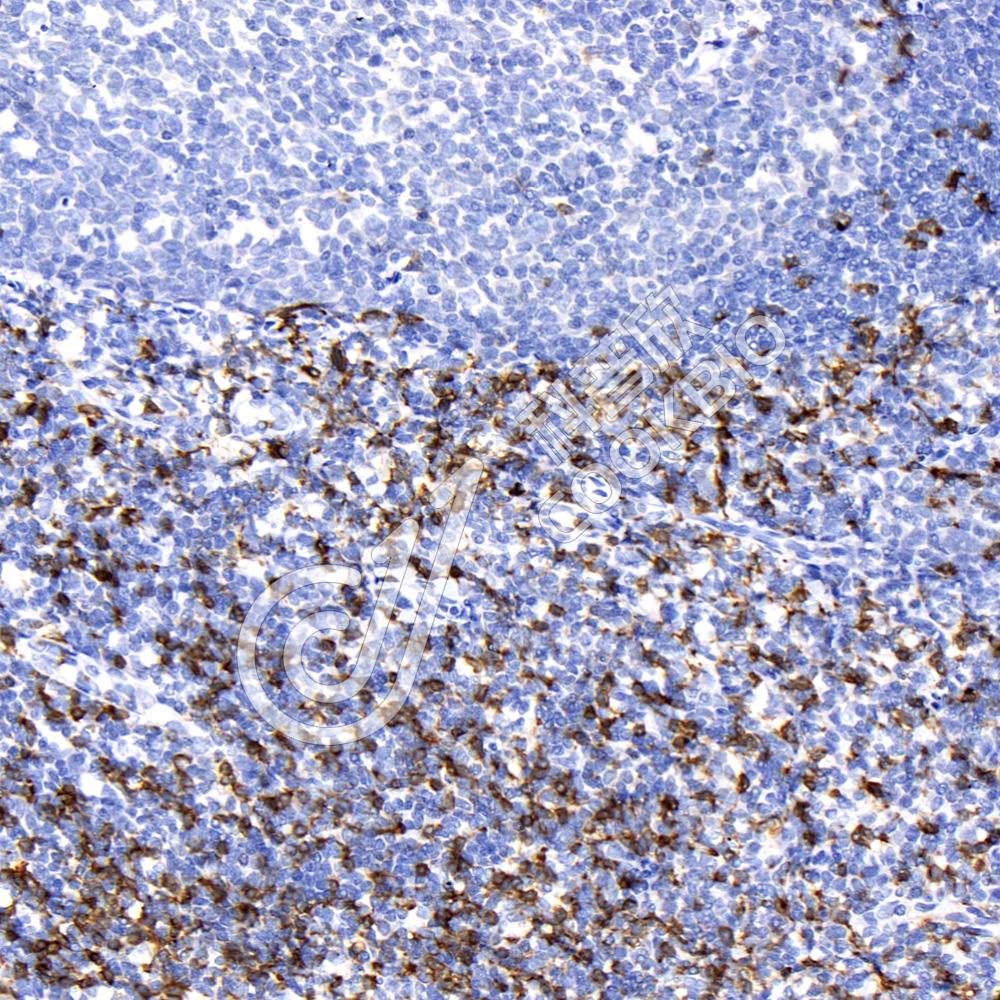

IHC检测CD8 alpha蛋白(货号 K236204).

样品: 人扁桃体, 4%多聚甲醛 (货号KSG1101) 固定12-24小时.

抗原修复: 柠檬酸抗原修复液(干粉, pH 6.0) (KSG1201), 高压锅均匀喷气计时2分钟.

—抗: 1: 2300稀释, 4℃ 孵育过夜.

二抗: S-vision免疫组化多聚二抗(山羊抗小鼠), 即用型(货号KB3903), 室温孵育20分钟.